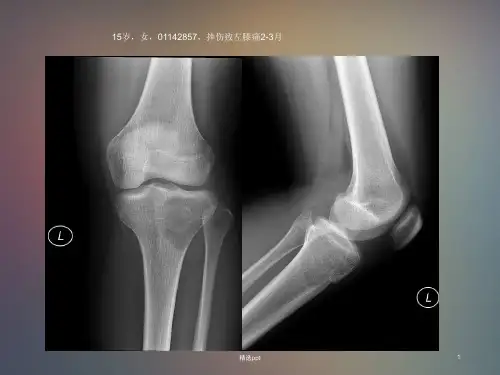

软骨母细胞瘤青少年10-20Y,四肢长管骨骨骺区,肱骨、股骨上端和胫骨近端好发,长骨骨骺端圆形、卵圆形骨质破坏,边缘不同程度硬化,其内常见斑点状、片状钙化。

软骨母细胞瘤X线、CT、MRI影像病理表现及治疗预后追踪分析摘要】目的探讨软骨母细胞瘤的影像学特征及临床、X线、CT、MRI表现及病理特点的诊断价值.方法分析82例经手术病理或穿刺活检证实的软骨母细胞瘤影像学资料表现及治疗后追踪预后复查. 【关键词】软骨母细胞瘤;放射摄影术;体层摄影术;X线计算机;核磁共振成像【中图分类号】R7【文献标识码】B【文章编号】1008-6315(2015)10-0104-02软骨母细胞瘤又名成软骨细胞瘤;定义为好发于骨骼发育阶段长骨骨骺的良性软骨性肿瘤(2002.WHO). 长期被认为属于巨细胞肿瘤Ewing首先于1923年报道,命名为钙化的巨细胞瘤Koloday(1927)、Ewing(1928)和Codman(1931)等认为它是巨细胞瘤的一种变异,以骨骺软骨性巨细胞瘤命名;Jaffe等(1942)提出,本病可能起源于软骨胚芽细胞,命名为良性软骨母细胞瘤,从而从骨巨细胞瘤中脱离出来目前多数学者认为CB起源于骺软骨细胞或残余骺1临床资料82例中男71例,女11例,年龄15-53岁,30岁以下75例.18例以局部包块就诊,37例局部不适、疼痛就诊,14例为外伤患者偶然发现,7例局部有压痛,6例皮肤稍红,皮温增高,疼痛、肿胀、关节活动受限. 2软骨母细胞瘤的X线、CT、MRI影像级病理分析2.1X 线平片和CT 典型的软骨母细胞瘤发生于骨骺,可跨越骺板累及干骺端,表现为分叶状或类圆形溶骨性骨破坏,内见斑点状、条状、团状和片絮状钙化,为软骨钙化和软骨化骨病灶边缘清楚,硬化,相邻骨皮质可有膨胀、变薄, 甚至消失,有时可见软组织肿块突出皮质轮廓之外.少数有骨膜反应,多为层状、条形. 软骨细胞瘤(CB)占原发良性骨肿瘤的1~2%,占骨良性肿瘤的3.46%;好发于10~25岁的年轻人,文献中最小病人3CB占原发良性骨肿瘤的1~2%, 占骨良性肿瘤的3.46%;好发于10~25岁的年轻人,文献中最小病人3岁,最大70岁;男性较多,男:女为2.2:1;临床表现:无特异性,疼痛、局部肿胀和活动受限为三大主要症状.个别患者可有胀痛或剧痛,夜间加剧;部分病例可有邻近关节活动受限,肢体麻木,邻近肌肉萎缩;部分患者在体检或外伤后行X 线检查时偶然发现病程在数月至数年2.2发病率、年龄和临床表现部位以股骨(33%)、肱骨(20%)和胫骨(18%)最常见,近一半发生于膝关节周围;有二次骨化中心的骨骺皆可发病,如发生于于颅底、胸椎、肩胛骨、肋骨、掌骨、颞骨、下颌骨及距骨等最多见的不典型部位为足部的跗骨和小管状骨好发于四肢长骨的骨骺及骨突,且多位于骨性关节面下;少数位于骺板者, 跨越骺板向两侧发展;极少数位于长管状骨的干骺端,与骨性关节面有一定距离,但多发生于骨骺融合后2.3发病部位镜下主要能观察到三种成分:软骨母细胞、多核巨细胞和软骨基质,原则上所有病例中均能观察到这三种成分;散在分布的多核巨细胞数量过多时往往造成病理误诊;钙盐沉着于软骨母细胞周围,形成“窗格样”钙化,曾被认为是CB的诊断要点,但仅见于1/3的病例;对于没有格子样钙化甚至没有任何钙化的病例,符合临床特点、影像表现及病理形态三要素,也能做出准确诊断. 因此格子样钙化是一种典型形态学特征,而不是诊断要点.2.4病理特征10~15%的CB合并动脉瘤样骨囊肿(ABC);合并ABC的病灶由许多大小不等的海绵样血腔组成,腔内充满流动的血液,此为与单纯肿瘤出血、坏死、囊变的主要区别;液-液平面提示合并ABC可能,但多数仍可见实性成分(与原发ABC不同);ABC范围大者掩盖原发病灶,依靠病理或免疫组化才能做出准确诊断另:35%的ABC 为继发性,最常继发于骨巨细胞瘤软骨母细胞瘤(CB)继发动脉瘤样骨囊肿(ABC) 绝大多数为良性,有一定的局部复发率(3.6%~38%不等),且有肺及全身多处骨转移并死亡的的报道,其机制目前还不清楚;虽有“恶性软骨母细胞瘤” 的病例报道,但其病理学所见与良性软骨母细胞瘤无明显区别,对恶性软骨母细胞瘤的认识仍比较模糊.病理不主张使用侵袭性软骨母细胞瘤的诊断,对局部浸润情况可以在诊断中加以注明;目前尚无明确组织学特点来预测其生物特性,仍需长期常规检查良恶性问题:CT:①部位:肿瘤局限在起源的骨骺处,多偏心性局限性生长,极少穿透骨骺软骨到达干骺端.病灶呈卵圆或圆形,表现为囊状透亮区,直径通常为2~4cm.②边界:肿瘤边缘清晰锐利,多有硬化带,与邻近正常骨界限明显.少数偏心性病灶可能膨胀致皮质变薄甚至断裂.到病程晚期,肿瘤具有侵袭性,骨破坏明显,并可侵入软组织,形成软组织块影.肿瘤可扩展至软骨下骨,但很少进入关节间隙.③钙化:肿瘤内部透亮,呈单房或有骨小梁间隔;一般早期无钙化,中期有的可见小点状、沙砾状钙化,晚期钙化明显并呈模糊疏松状不规则分布,但无巨细胞瘤具有的明显骨小梁分隔改变.④一般无骨膜反应;⑤可有坏死囊变;MRI: 在MRI上的信号与病理密切相关.在T1WI 上,CB表现为不均匀中等或低信号以等、低信号为主,T2WI上信号则呈混杂信号,与病灶内各种细胞成分的比例有关,软骨样基质通常呈较高的信号,伴发动脉瘤样骨囊肿则呈明亮的高信号,出血后囊变也呈高信号,钙化、出血后形成的含铁血黄素则呈低信号. 病灶边缘在T1WI、T2WI呈连续或不连续的低信号环,病理上为肿瘤缓慢生长引起的反应性成骨. 周围可见大片状骨髓水肿,边缘模糊,多跨越骺板;骨髓水肿的病理基础可能由于肿瘤细胞释放的前列腺素,刺激骨髓中纤维血管组织的增生和血管周围淋巴细胞和血浆细胞的渗出,为非特异性改变;病灶切除后炎性反应随之消退,若病灶复发,则又复出血,故可监测肿瘤复发.MRI另一优势在于可以清晰显示肿瘤突破骨皮质形成的团状软组织肿块,还可清晰显示关节软组织的肿胀及关节腔的积液3鉴别诊断少见部位的CB(髌骨CB合并ABC): 出现以下表现时,应高度怀疑恶变或原发恶性软骨母细胞瘤可能:1.局部肿块病史较长,近来生长突然加快;2.病灶外形、轮廓不规则;3.骨破坏区与正常骨分界不清,或虽分界清楚但无硬化带;4.骨皮质破坏较明显,伴有软组织肿块,其内可见环状及半环状高密度影;5.出现大量不规则骨膜反应等状及半环状高密度影;5.出现大量不规则骨膜反应等4.1骨巨细胞瘤软骨黏液样纤维瘤透亮度较高,多位于干骺端,偏心性囊性扩张明显,常侵蚀皮质层或从皮质气球状凸出,内可见粗厚的骨嵴,大囊套小囊,近骨干侧皮质显著增厚. 4.2内生软骨瘤(单发) 内生软骨瘤发病高峰年龄段为20~40岁,多位于长管状骨干骺端,肿瘤形态不规则,缺乏明确硬化边、骨膜增生和软组织肿胀. 4.3软骨肉瘤软骨肉瘤多见于中老年患者,多位于骨盆或长管状骨干骺端,T2WI多呈显著高信号,低信号成分少见,缺乏硬化边. 4.4结核应注意与关节结核相鉴别,尤其是病变侵犯关节软骨时,引起邻近关节的反应,出现疼痛、积液,又为单关节发病,以及对X线片表现认识不足时易与关节结核相混淆主要以临床症状,肺部检查,实验室检查. 4.5软骨性病变的共同影像特征软骨基质X线表现为分叶状低密度.软骨钙化:点状、斑块状、条索状、弧状、半环和环状MRI 信号特征:T1WI呈偏低信号,T2WI呈分叶状高信号,有低信号间隔分隔.4小结软骨母细胞瘤是来源于骨骺、较少见的原发良性肿瘤,但它有局部复发、转移及恶变可能,应综合临床表现、影像特征及病理形态等进行争端,并做相应的外科之劳,尽可能避免复发或转移.参考文献[1]葛英辉,黄兆民,肖官惠,等,成软骨细胞瘤影像学诊断[J].中华医学杂志,1992.72(6).357. [2]孙英彩,崔建玲,李石玲,等.软骨母细胞瘤临床及CT 表现[J].实用放射学杂志,2003,19(7):608-610. [3]高德培,丁莹莹,谭静,等.16层螺旋CT后处理技术在骨肿瘤诊断中的价值.中国CT和 MRI杂志,2006,4(2):39-45. [4]徐爱德,徐文坚,刘吉华.骨关节CT 和MRI诊断学[M].济南:山东科技出版社,2002,157-160. [5]RamappaAT,LeeFY,TangP,etal.Chondroblastomaofbone[J].Jbone[ JonitSurg,2000,82(A):1140-114.6]杨世勋.软骨母细胞瘤临床影像学表现与病理分析[J].中国医学计算机成像杂志,2006,7(3)164-166. [7]刘子君,主编.骨关节病理学[M].北京:人民卫生出版社,2000,180.。